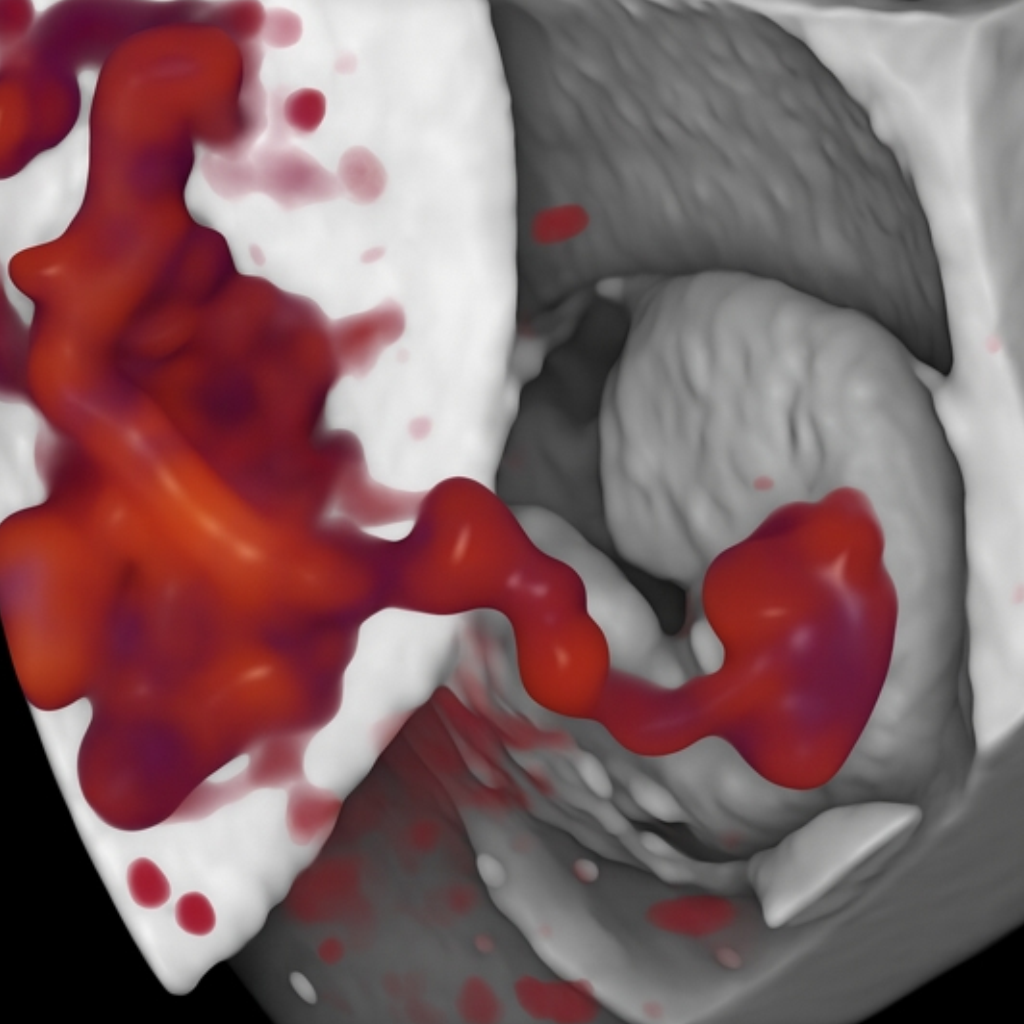

Entre 25 e 26 semanas: Melhor época para o exame 3D/4D/5D.

Entre 26 e 28 semanas: Ecocardiografia fetal – o rastreio completo do coraçãozinho do seu bebê.

Ultrassom de última geração!

Aparelho de ultrassom de última geração, com mais tecnologia, capaz de capturar imagens em 3D/4D/5D ultrarrealistas. Chega de visualizar seu bebê em preto e branco, na Clínica Ecoa você poderá ver cada detalhe com nitidez incomparável, vivenciando um dos momentos mais especiais da maternidade de forma única. Garantimos exames precisos e uma experiência inesquecível.